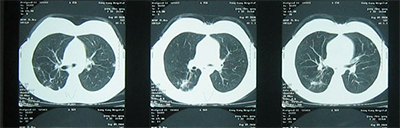

2016年1月10日,楊某某就診于我院,輔助檢查血常規(guī)、血沉、肝功、腎功、血糖、電解質(zhì)均未見明顯異常。C-反應(yīng)蛋白9mg/L;TB-AB:1+;痰涂片示:4+。并做藥敏。胸部CT示:雙肺結(jié)核并空洞。

2016年1月10日(剛來我院時):